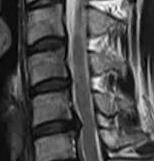

强直性脊椎炎能够致残,是不是觉得有点骇人听闻?可以直接的对你说,这是真的。由于强直性脊椎炎一般先侵犯骶髂关节,然后沿脊柱逐渐向上发展,而累及腰椎、胸椎、甚至颈椎受累脊柱不仅出现腰背疼痛,而且可同时出现进行性关节及脊柱活动功能受限,如病情进一步发展,则可使椎间盘、关节突及椎间各韧带都会发生骨化。在X线片上显示脊柱形成竹节状的骨性强直,有的则形成不同程度的驼背畸形,严重者不仅行动不便,而且两眼只能看地面的问号体形。贵州专业治疗强直医院

强直性脊柱炎危害常识有哪些?强直性脊椎炎大约有60%以上出现髋关节受累,它不仅可使髋关节间隙变狭窄、而且可引起骨质破坏导致髋关节疼痛,髋关节不敢做屈伸活动,久之则致髋关节骨性强直,而失去活动功能,造成终身残废。由于髋关节受损而致残的患者约占强直性脊椎炎患者中的15%-20%。只有50%左右的病人可维持工作和生活能力,但终身伴有各种不同程度的不适、痛苦和不便。